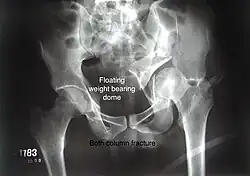

Both column fracture showing floating weight bearing dome -

Combined both column fractures | These are the most complex injuries. Here the weight bearing roof or dome of the acetabulum is a floating piece. This adds to complexity of management.